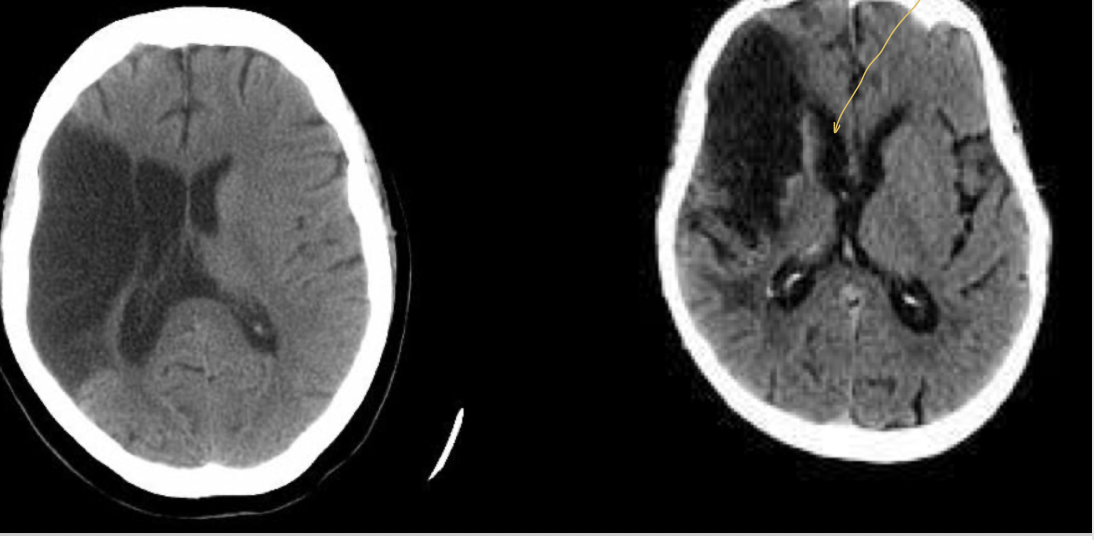

13

Diagnóstico:

A

EVC isquémico en fase hiperaguda

14

Diagnóstico

Características del EVC isquémico en fase hiperaguda

De 0 a 6 hrs

En 60% de los casos la TC sin datos de ACM (arteria cerebral media) hiperdensa

Signo de la cinta insular

Qué es el signo de la cinta insular

Pérdida de diferenciación de la sustancia gris y blanca en una TC vista en el EVC isquémico en fase hiperaguda